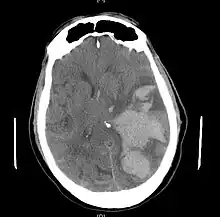

Treatment

Treatment involves removal of the etiologic mass and decompressive craniectomy. Brain herniation can cause severe disability or death. In fact, when herniation is visible on a CT scan, the prognosis for a meaningful recovery of neurological function is poor.[2] The patient may become paralyzed on the same side as the lesion causing the pressure, or damage to parts of the brain caused by herniation may cause paralysis on the side opposite the lesion.[11] Damage to the midbrain, which contains the reticular activating network which regulates consciousness, will result in coma.[11] Damage to the cardio-respiratory centers in the medulla oblongata will cause respiratory arrest and (secondarily) cardiac arrest.[11] Investigation is underway regarding the use of neuroprotective agents during the prolonged post-traumatic period of brain hypersensitivity associated with the syndrome.[17]